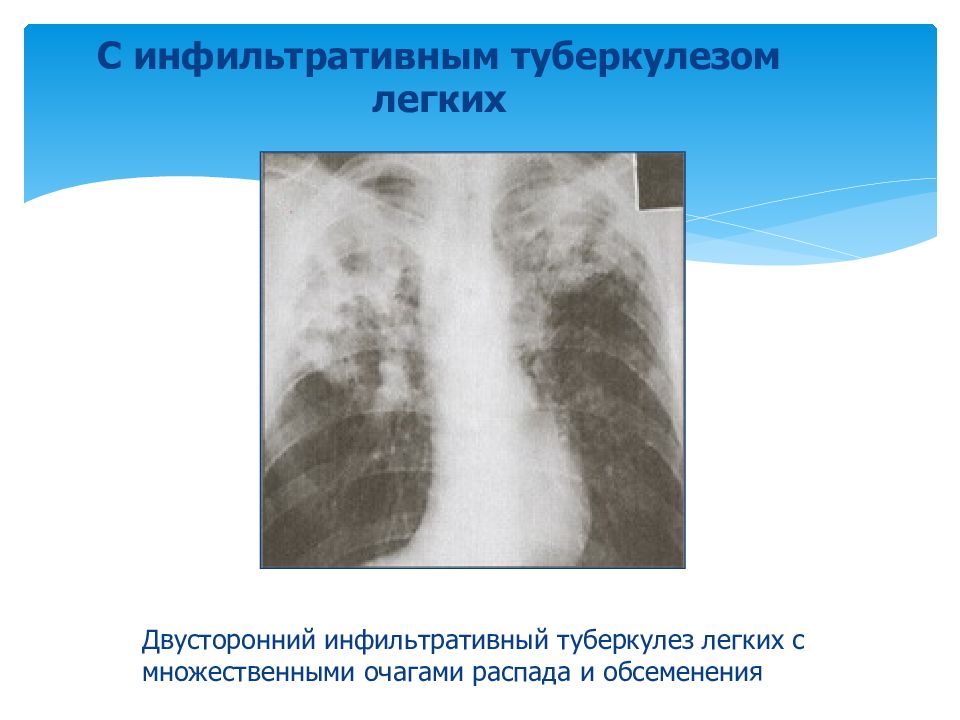

Очаговый и инфильтративный туберкулез презентация - 94 фото